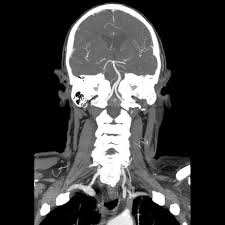

Subclavian steal syndrome definition. Look it up now. Subclavian Steal Syndrome SSS is a condition that results from subclavian artery stenosis proximal to the origin of the vertebral artery. Subclavian steal syndrome implies the presence of significant symptoms due to arterial insufficiency in the brain ie vertebrobasilar insufficiency or upper extremity which is supplied by the subclavian artery figure 1.

Subclavian Steal Syndrome SSS which is the reverse flow from vertebral artery to subclavian artery was first described in 1977 with an incidence of 044. In medicine subclavian steal syndrome also called subclavian steal phenomenon or subclavian steal steno-occlusive disease is a constellation of signs and symptoms that arise from retrograde flow of blood in the vertebral artery or the internal thoracic artery due to a proximal stenosis andor occlusion of the. A clinically significant reduction in blood supply to the BRAIN STEM and CEREBELLUM ie VERTEBROBASILAR INSUFFICIENCY resulting from reversal of blood flow through the VERTEBRAL ARTERY from occlusion or stenosis of the proximal subclavian or brachiocephalic artery.

Subclavian steal syndrome is defined as stenosis or occlusion of the subclavian artery proximal to the origin of the vertebral artery with consequent reversal of blood flow in the vertebral artery to supply the distal subclavian artery resulting in neurologic symptoms. The symptoms of cerebral vascular insufficiency not enough blood to the brain when the patient exercises an arm due to obstruction of the subclavian artery before the origin the takeoff of the vertebral artery. In summary subclavian steal syndrome is blood flow reversal in vertebral arteries usually caused by severe stenosis of the subclavian artery or innominate artery.